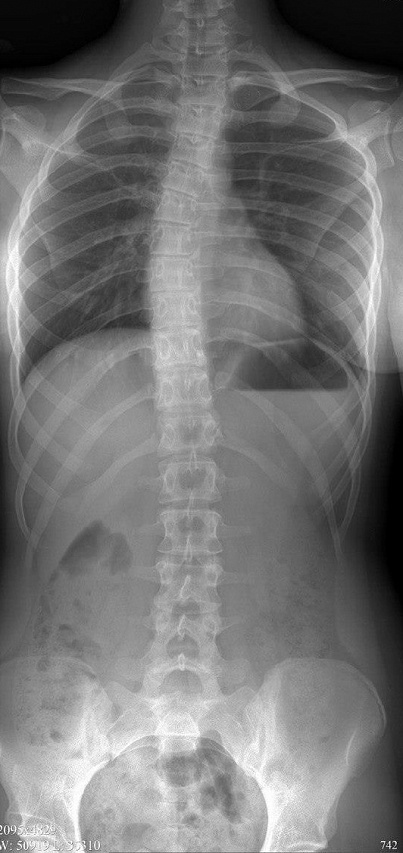

За полтора года работы было проведено более 8 тыс исследований, в том числе трудоемких, таких как панорамная рентгенография позвоночника, конечностей. Данная процедура длится около 10 минут, а дальнейшая цифровая обработка позволяет получить панорамное исследование в высоком качестве. В результате при одном исследовании врач-рентгенолог имеет возможность оценить костные структуры сразу нескольких областей, что особенно важно при оценке аномалии развития позвоночника и конечностей.